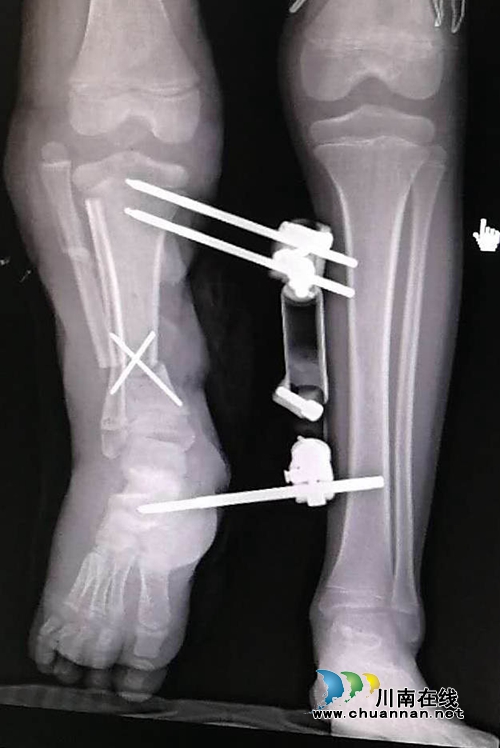

2015年12月,邹永根教授带领的团队为萌萌实施了右小腿毁损性离断伤短缩断肢体再植+右小腿碾压切开减压VSD治疗术,手术很成功,萌萌的右腿保住了。但新的问题又来了:由于碾压伤过重,手术后的萌萌右腿比左腿短了足足15厘米!这对萌萌来说,无疑又是一个打击。

2016年4月,家人带着萌萌再次来到骨伤科(矫形·儿骨·手外组),邹永根教授建议给萌萌用Ilizarov支架做肢体延长手术治疗。手术后,随着时间的推移,经历7个月缓慢延长萌萌的右腿,最终延长了15厘米,但延长肢体的骨骼需要1-2年的矿化塑形时间。期盼回到学校的萌萌手术后不到一年,就带着钢铁支架上学去了。